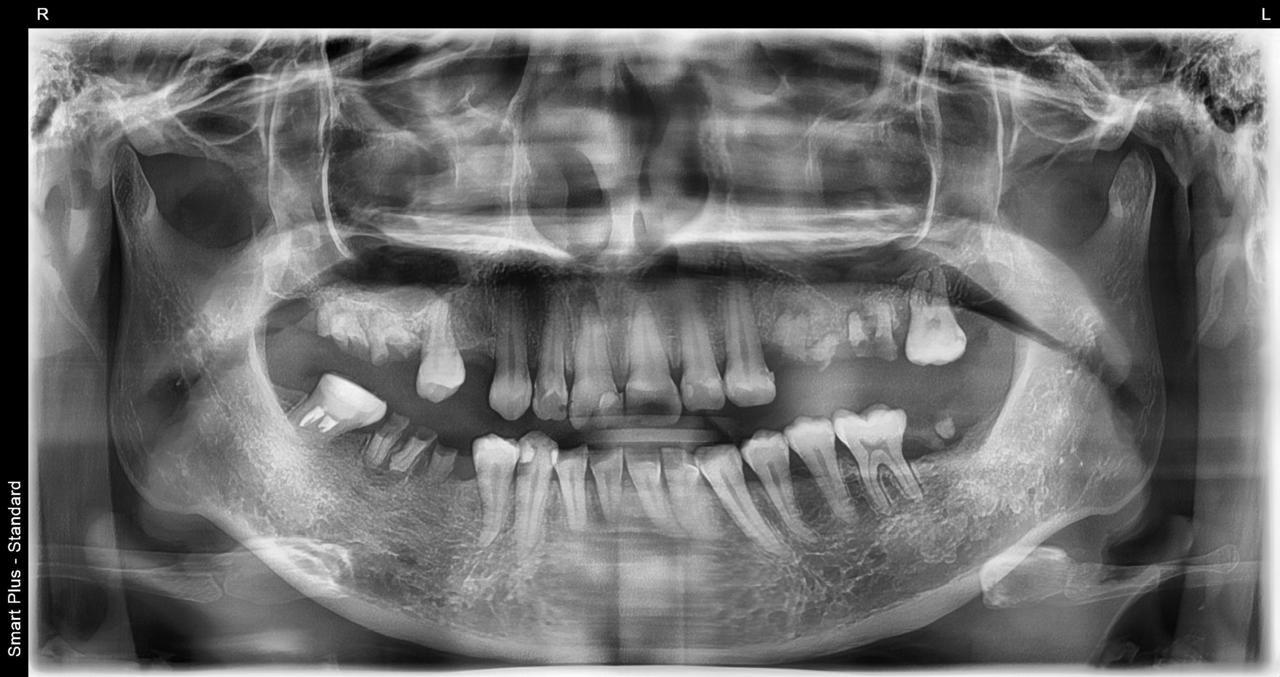

Before

枚方市のインプラントの症例

M・I 様 女性 70代

症状としては、左下56は、歯周病で欠損したと考えられるが、かなりの骨欠損をともなっていた。左上456に関しては、動揺が大きく、炎症が起き、排膿、および、歯性上顎洞炎を起こしていた。

治療法としては、動揺がひどくなってきて、炎症の症状もあったため、左上56の抜歯を希望。インプラント治療をその後、希望したため、左上4に関しては抜歯即時埋入。左上6に関しては、既存骨1から2mmでインプラント治療が厳しい状態であったが、グラフトレスサイナスリフトを行い、治療期間5か月はかかるということを説明して、インプラント埋入をおこないました。その後、2か月半後、大幅に骨が欠損している下顎56に対して、ショートインプラントを使用して、下顎神経の損傷を避けて、インプラント埋入を終えています。その後2か月後に光学印象で印象を行い、上顎刺億456歯、3ユニットのジルコニアブリッジを装着。下顎左側56に関しては、骨欠損が大きいため、歯冠長がだいぶ長くなるため、ジルコニアの連結冠を装着して治療を終えた。

治療結果は、上顎6に関しては、既存骨が少なく、厳しい治療ではありましたが、5か月で治療を終え、患者様の負担を最小限に抑えるができたと考えます。(従来のサイナスリフトでは、このようなケースでは1年以上、1年程度の治療期間がかかるか、治療が不可能と言われるケースだと考えます。)また、下顎は骨欠損が大きく、下歯槽管のリスクが起きることが考えられますが、ショートインプラントを使用することで安全に治療を行うことができました。

治療の期間・回数:治療期間5か月(上顎456 3ピースブリッジの治療は5か月(上顎既存骨が2mm程度しかなく、骨結合に時間がかかるケースであったために、5か月の治療期間が必要であった。)(左下56に関しては2か月半で治療を終えています。)治療回数は、13回。

治療の価格:1,474,000円(税込)

治療費の内訳:左上46および左下56のインプラント基本料(フィックスチャー及び手術費用、投薬費用、レントゲン費用、インプラント上部費用(アバットメントおよびジルコニアクラウンの費用用)330000円(税込み)×4本分 1320000円(税込)。左上5ジルコニアポンテック費用88000円(税込)。オプション費用、左上4抜歯即時埋入加算(人工骨費用を含む)+グラフトレスサイナスリフト費用 33000円(税込)、左上6グラフトレスサイナスリフト費用 33000円(税込)